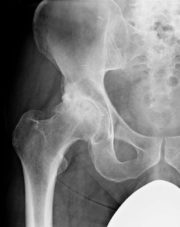

Hüftgelenksarthrose (Coxarthrose)

Unter Hüftgelenksarthrose (Coxarthrose) versteht man einen Verschleiß des Knorpelüberzuges an Oberschenkelkopf und Hüftgelenkpfanne. Normalerweise gewährleistet der intakte Knorpel durch seine glatte Oberfläche eine schmerzfreie Bewegung im Hüftgelenk. Durch den defekten Knorpel kommt es zu vermehrter Reibung, welche Schmerzen verursacht. Patienten mit Hüftarthrose verspüren meist einen Schmerz im Bereich der Leistenregion, begleitend kann eine Schmerzausstrahlung in den Oberschenkel bestehen. Durch die vier Kardinalsymptome Nachtschmerz, Ruheschmerz, Anlaufschmerz und einer eingeschränkten Gehstrecke ist die Lebensqualität der Patienten deutlich eingeschränkt. Begleitend besteht auch eine Bewegungseinschränkung des Hüftgelenkes, so kann bereits das Anziehen von Socken oder Schuhen erschwert sein.

Die Ursachen der Arthrose sind vielfältig. Meist besteht aber ein altersbedingter Verschleiß des Knorpels. Andererseits kann eine nicht erkannte Hüftdysplasie im Kindesalter durch eine ungünstige Gelenksituation zu einer vorzeiten Hüftarthrose führen. Bei Rheumapatienten kommt es hingegen zu einer fehlgesteuerten Immunabwehr gegen das eigene Gelenk. Durch die Entzündungsreaktion wird das Gelenk zerstört. Eine andere Ursache kann eine Durchblutungsstörung des Hüftkopfes durch die langfristige Einnahme von Cortison oder z. B. übermäßiger Alkoholgenuss sein. Hierunter kommt es zu einem Absterben des Hüftkopfes (sog. Hüftkopfnekrose).

Durch Unfälle kann es zu Schädigungen des Hüftkopfes oder Gelenkpfanne kommen. Insbesondere bei fehlerhaft ausgeheilten Brüchen mit Beteiligung des Knorpels kommt es zur Arthrose.